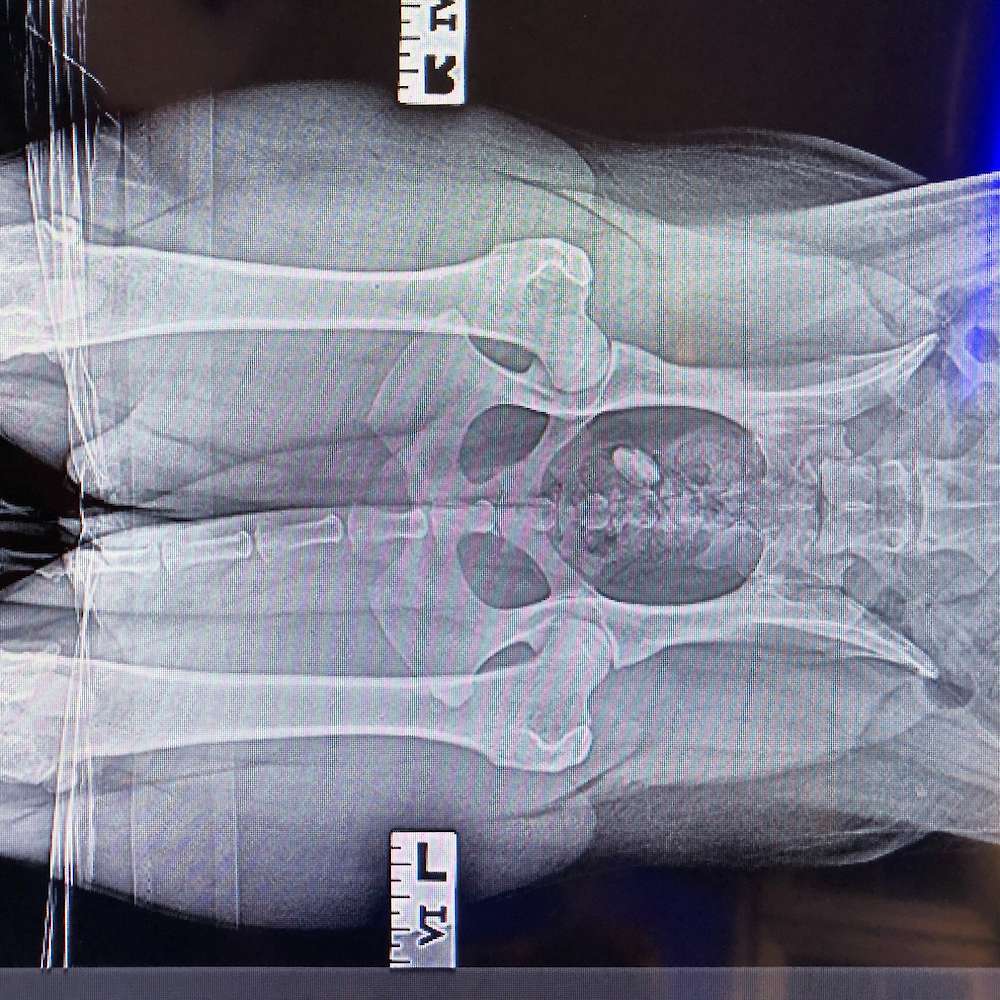

Pipers hip xrays